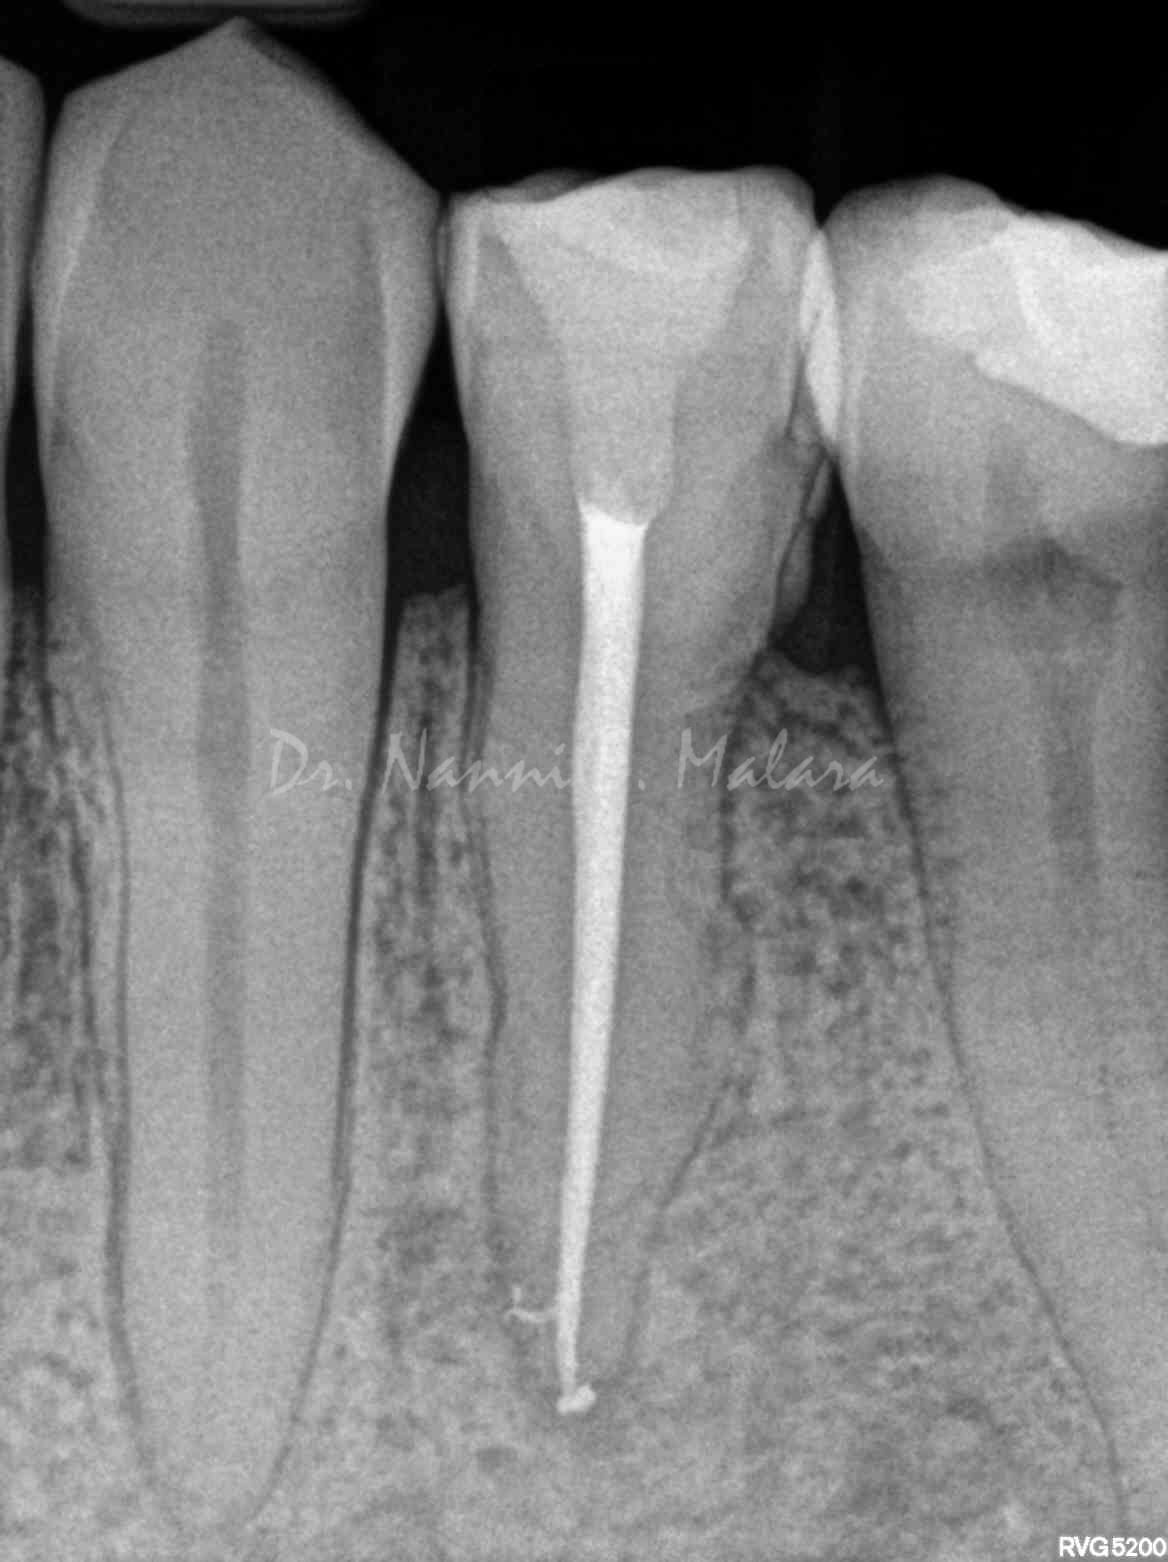

Terapia endodontica con sigillo tridimensionale dei canali radicolari

Controllo della guarigione a 7 mesi dalla terapia endodontica (Alla radiografia si nota come le lesioni ossee siano guarite, e la densità della trabecolatura ossea sia tornata alla normalità)